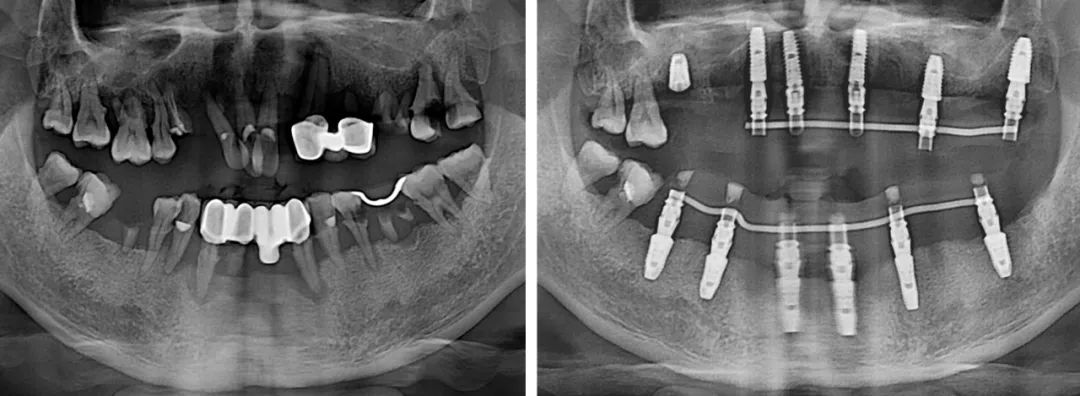

短短幾年,劉今朝已完成種植修復(fù)治療上千例,成長速度比絕大多數(shù)同齡醫(yī)生更快。工作以來,他已多次公派參加專業(yè)培訓(xùn)和學(xué)術(shù)會議,同時,也完成了從常規(guī)種植到半口全口無牙頜種植的技術(shù)進(jìn)階。

“做種植牙,良好的咬合是最終目的。相對單顆、多顆種植,半口咬合重建難度更大。半口種植的患者往往對側(cè)牙齒也不是特別好,種植后如何調(diào)整咬合,非??简炨t(yī)生的水平。”

技術(shù)進(jìn)階,意味著難度也有了進(jìn)階,不管遇到什么樣的病例,劉今朝始終牢記“修復(fù)是種植的目的”這一原則,以最終的修復(fù)效果為目標(biāo),來指導(dǎo)整個治療。